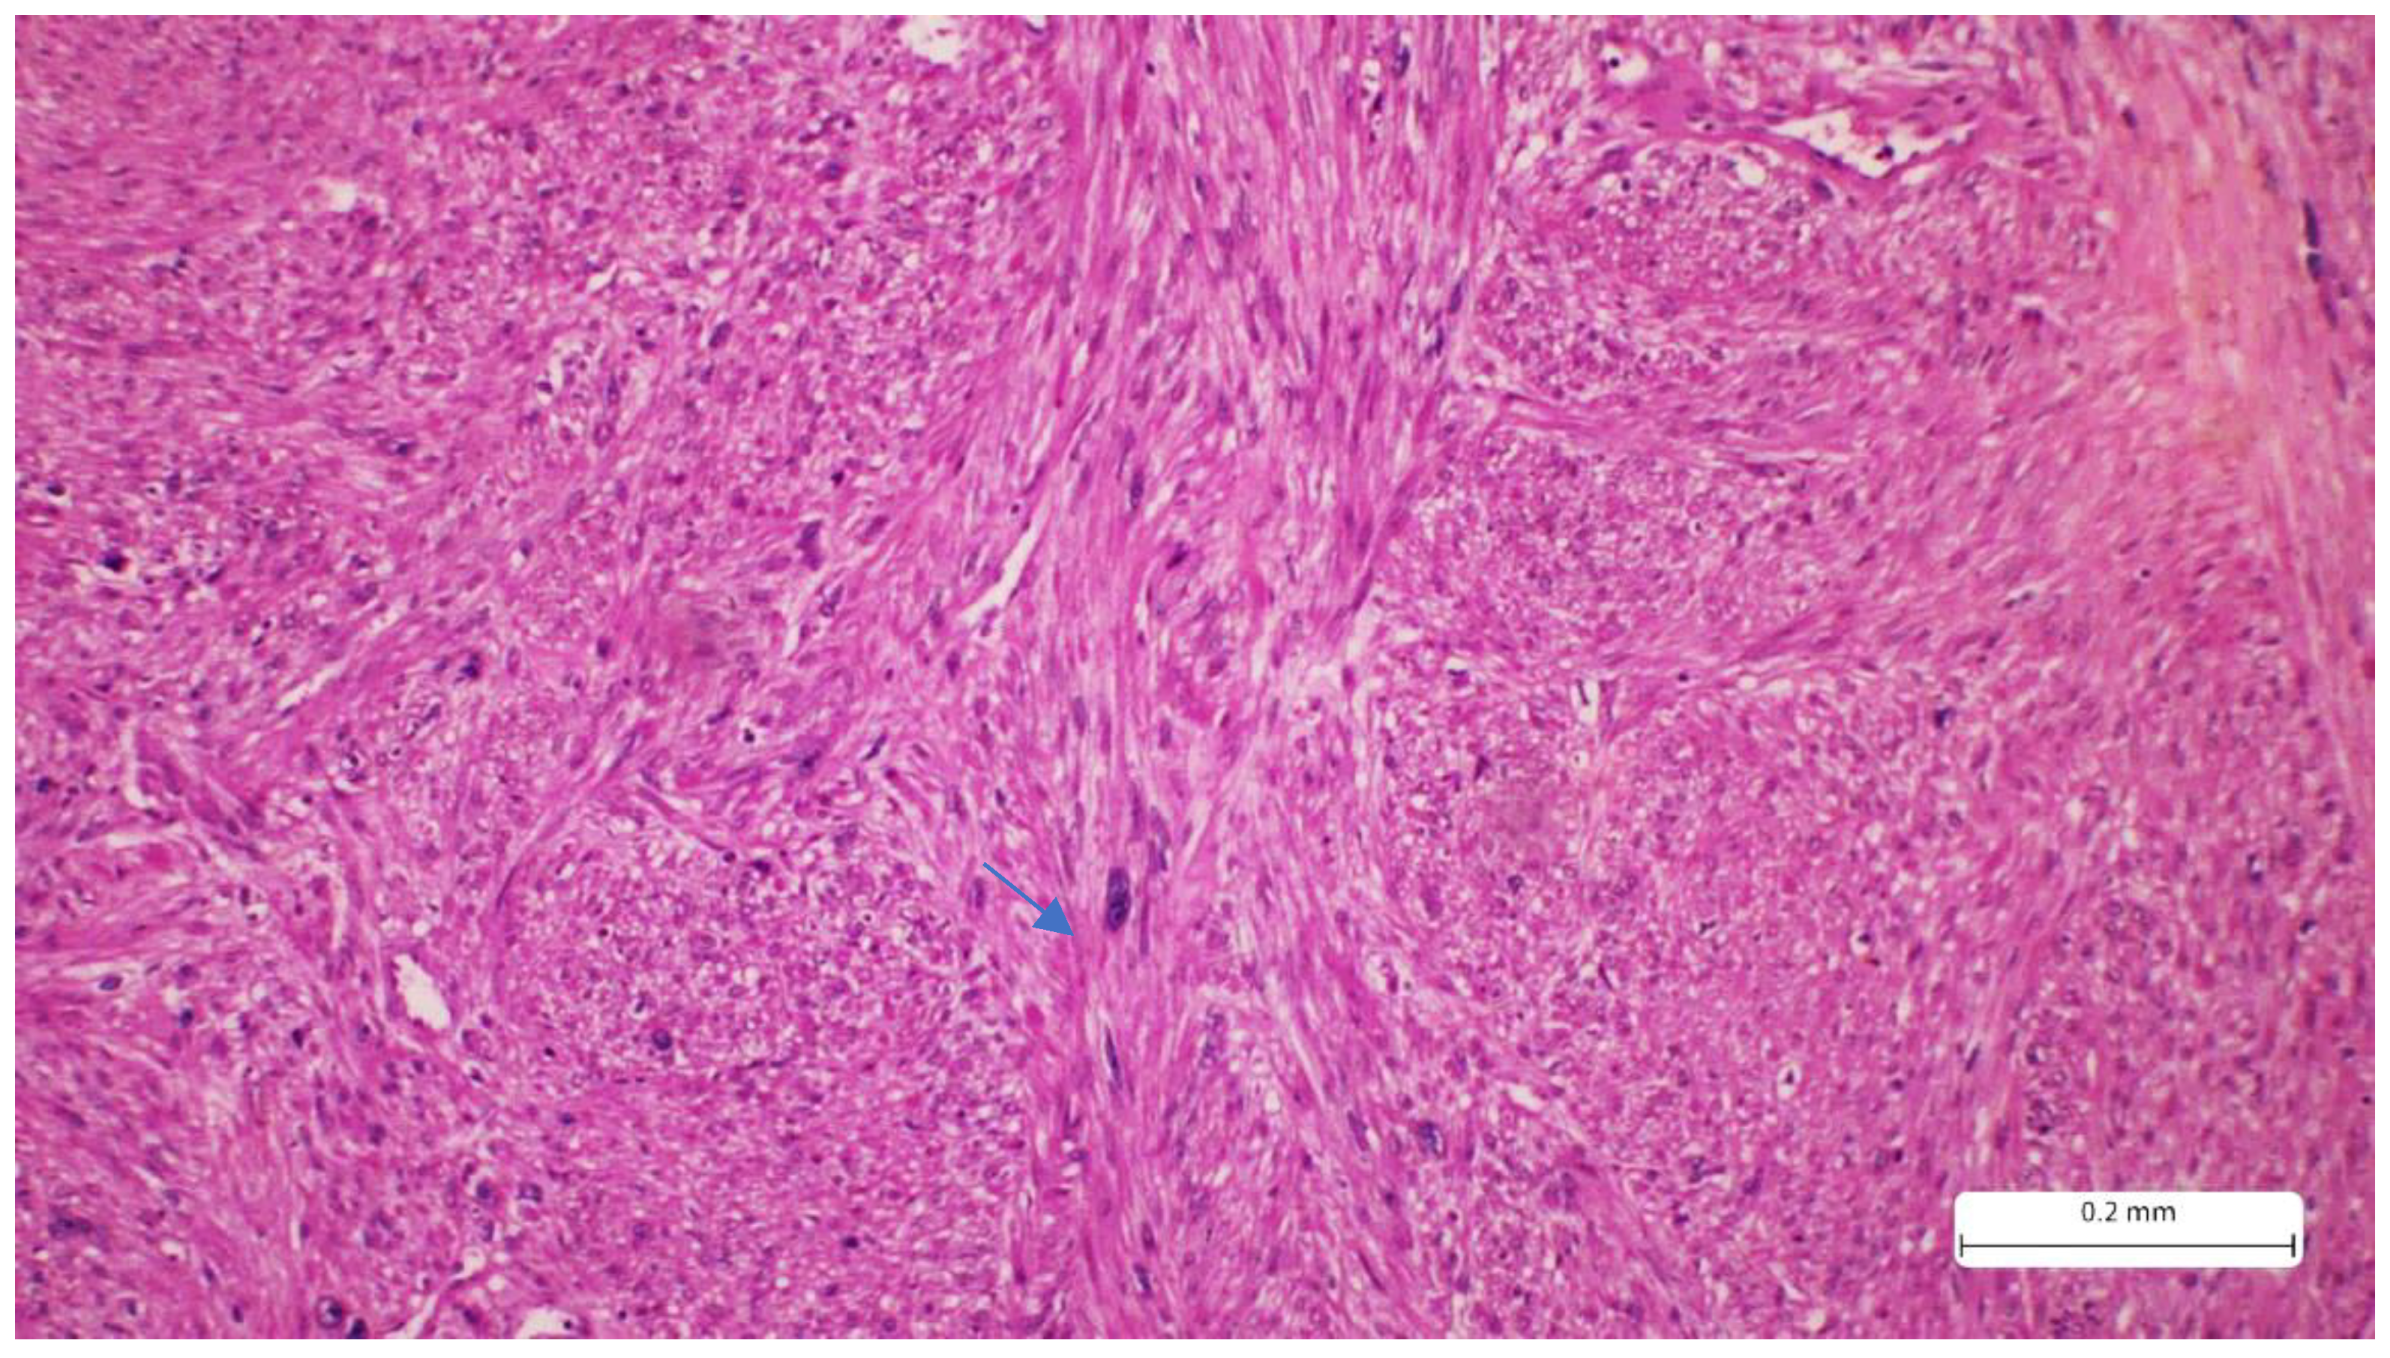

Recurrent Cutaneous Leiomyosarcoma: A Histopathological Perspective and the Quest for Complete Excision

2. Case Report